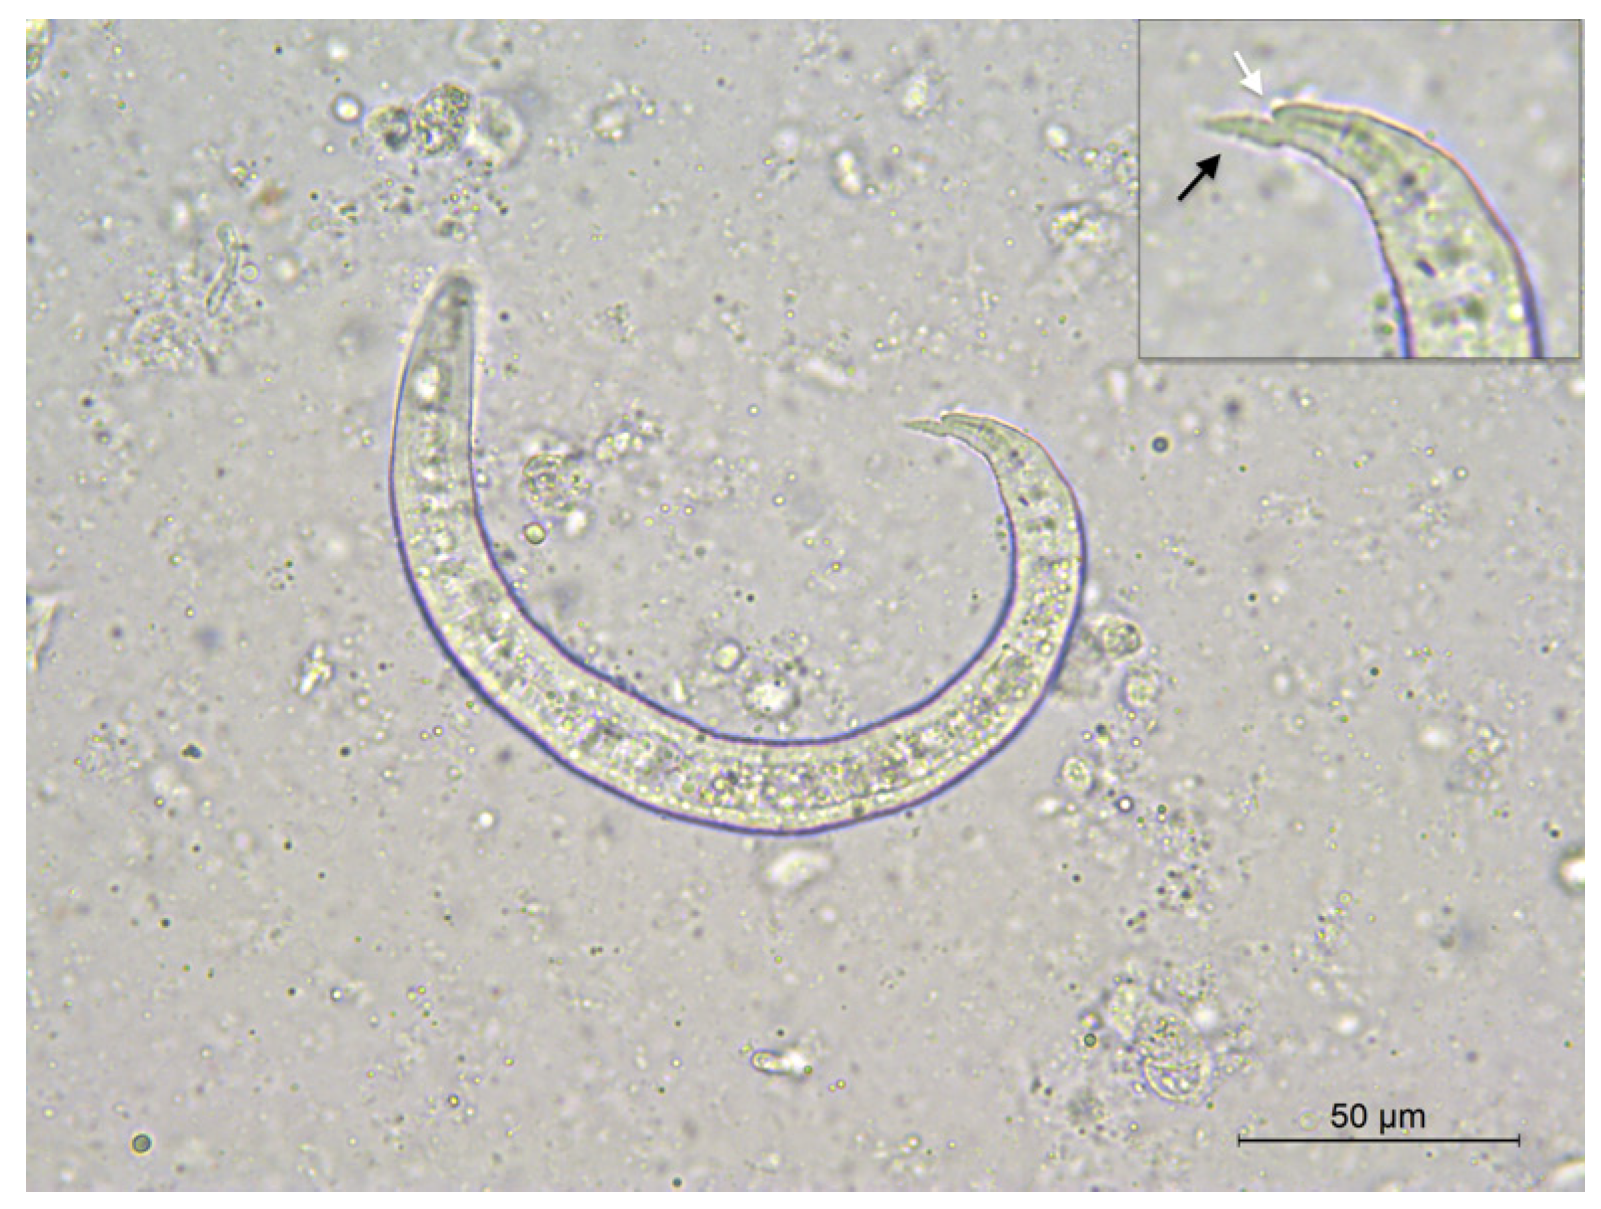

The first-stage larvae of A. vasorum were microscopically observed in the impression smears of the lungs (Figure 4). Adult nematodes retrieved in the right heart ventricle were washed and stored in 70% ethanol until morphological and molecular identification. Two adult female species were identified as A. vasorum, based on the size and typical morphology of ovaries, wrapped in a coil around the intestine [2]. Their identification was subsequently confirmed by individual genetic analysis.

Figure 4.

Angiostrongylus vasorum first-stage larva in impression smears of lungs. Note the pointed and slightly sinusoidal tail (black arrow) with dorsal indentation (white arrow).